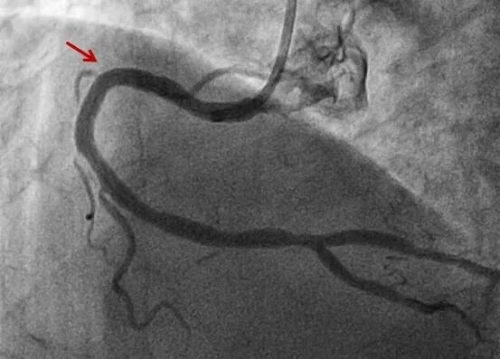

【山好水好人更好】州医院成功抢救七旬东北突发重症游客